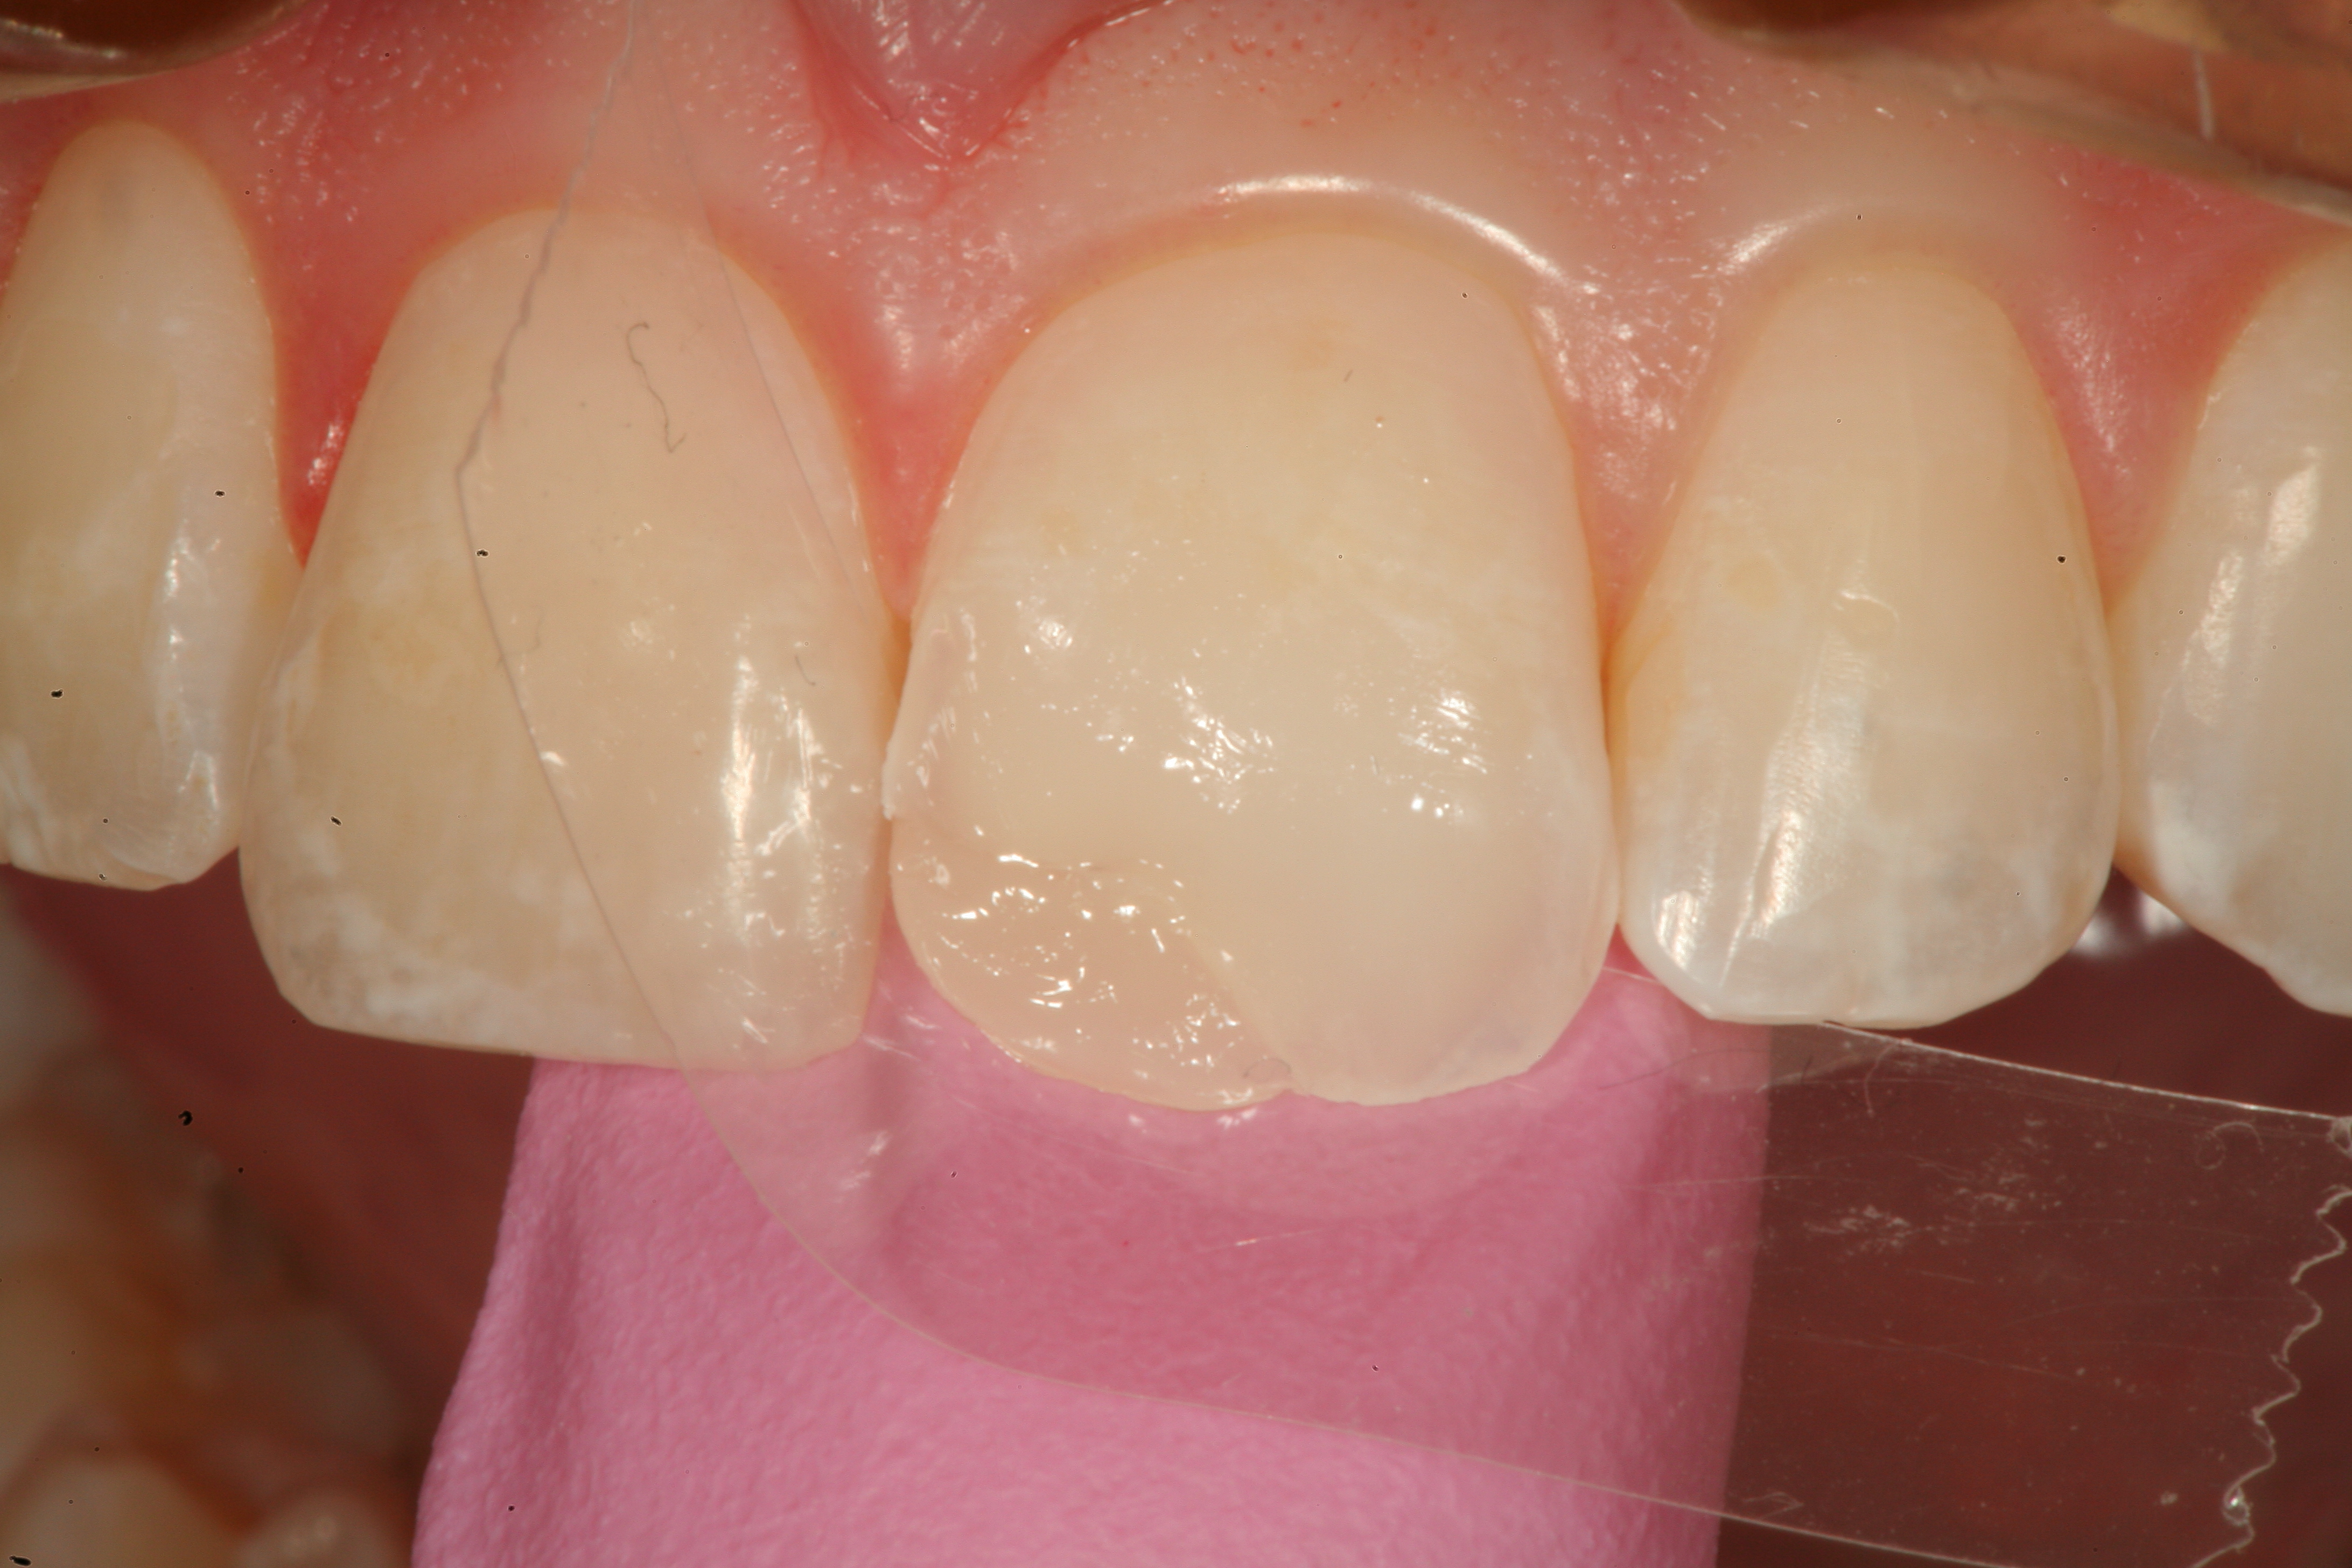

Fig 20. A distal-occlusal cavity preparation in tooth No. 29 and a mesial-occlusal-distal cavity preparation in tooth No. 30 are both shown from the occlusal aspect. A diode laser has been used interproximally to create supragingival margins to aid in precise gingival placement of the restorative material.

Figure 20

Fig 21. A Giomer bulk-fill paste-type composite is shown being placed with a composite placement instrument in the distal-occlusal cavity preparation on tooth No. 29.

Figure 21

Fig 22. A sable artists’ brush is used to smooth the composite material over the restorative margins before light-curing the material.

Figure 22